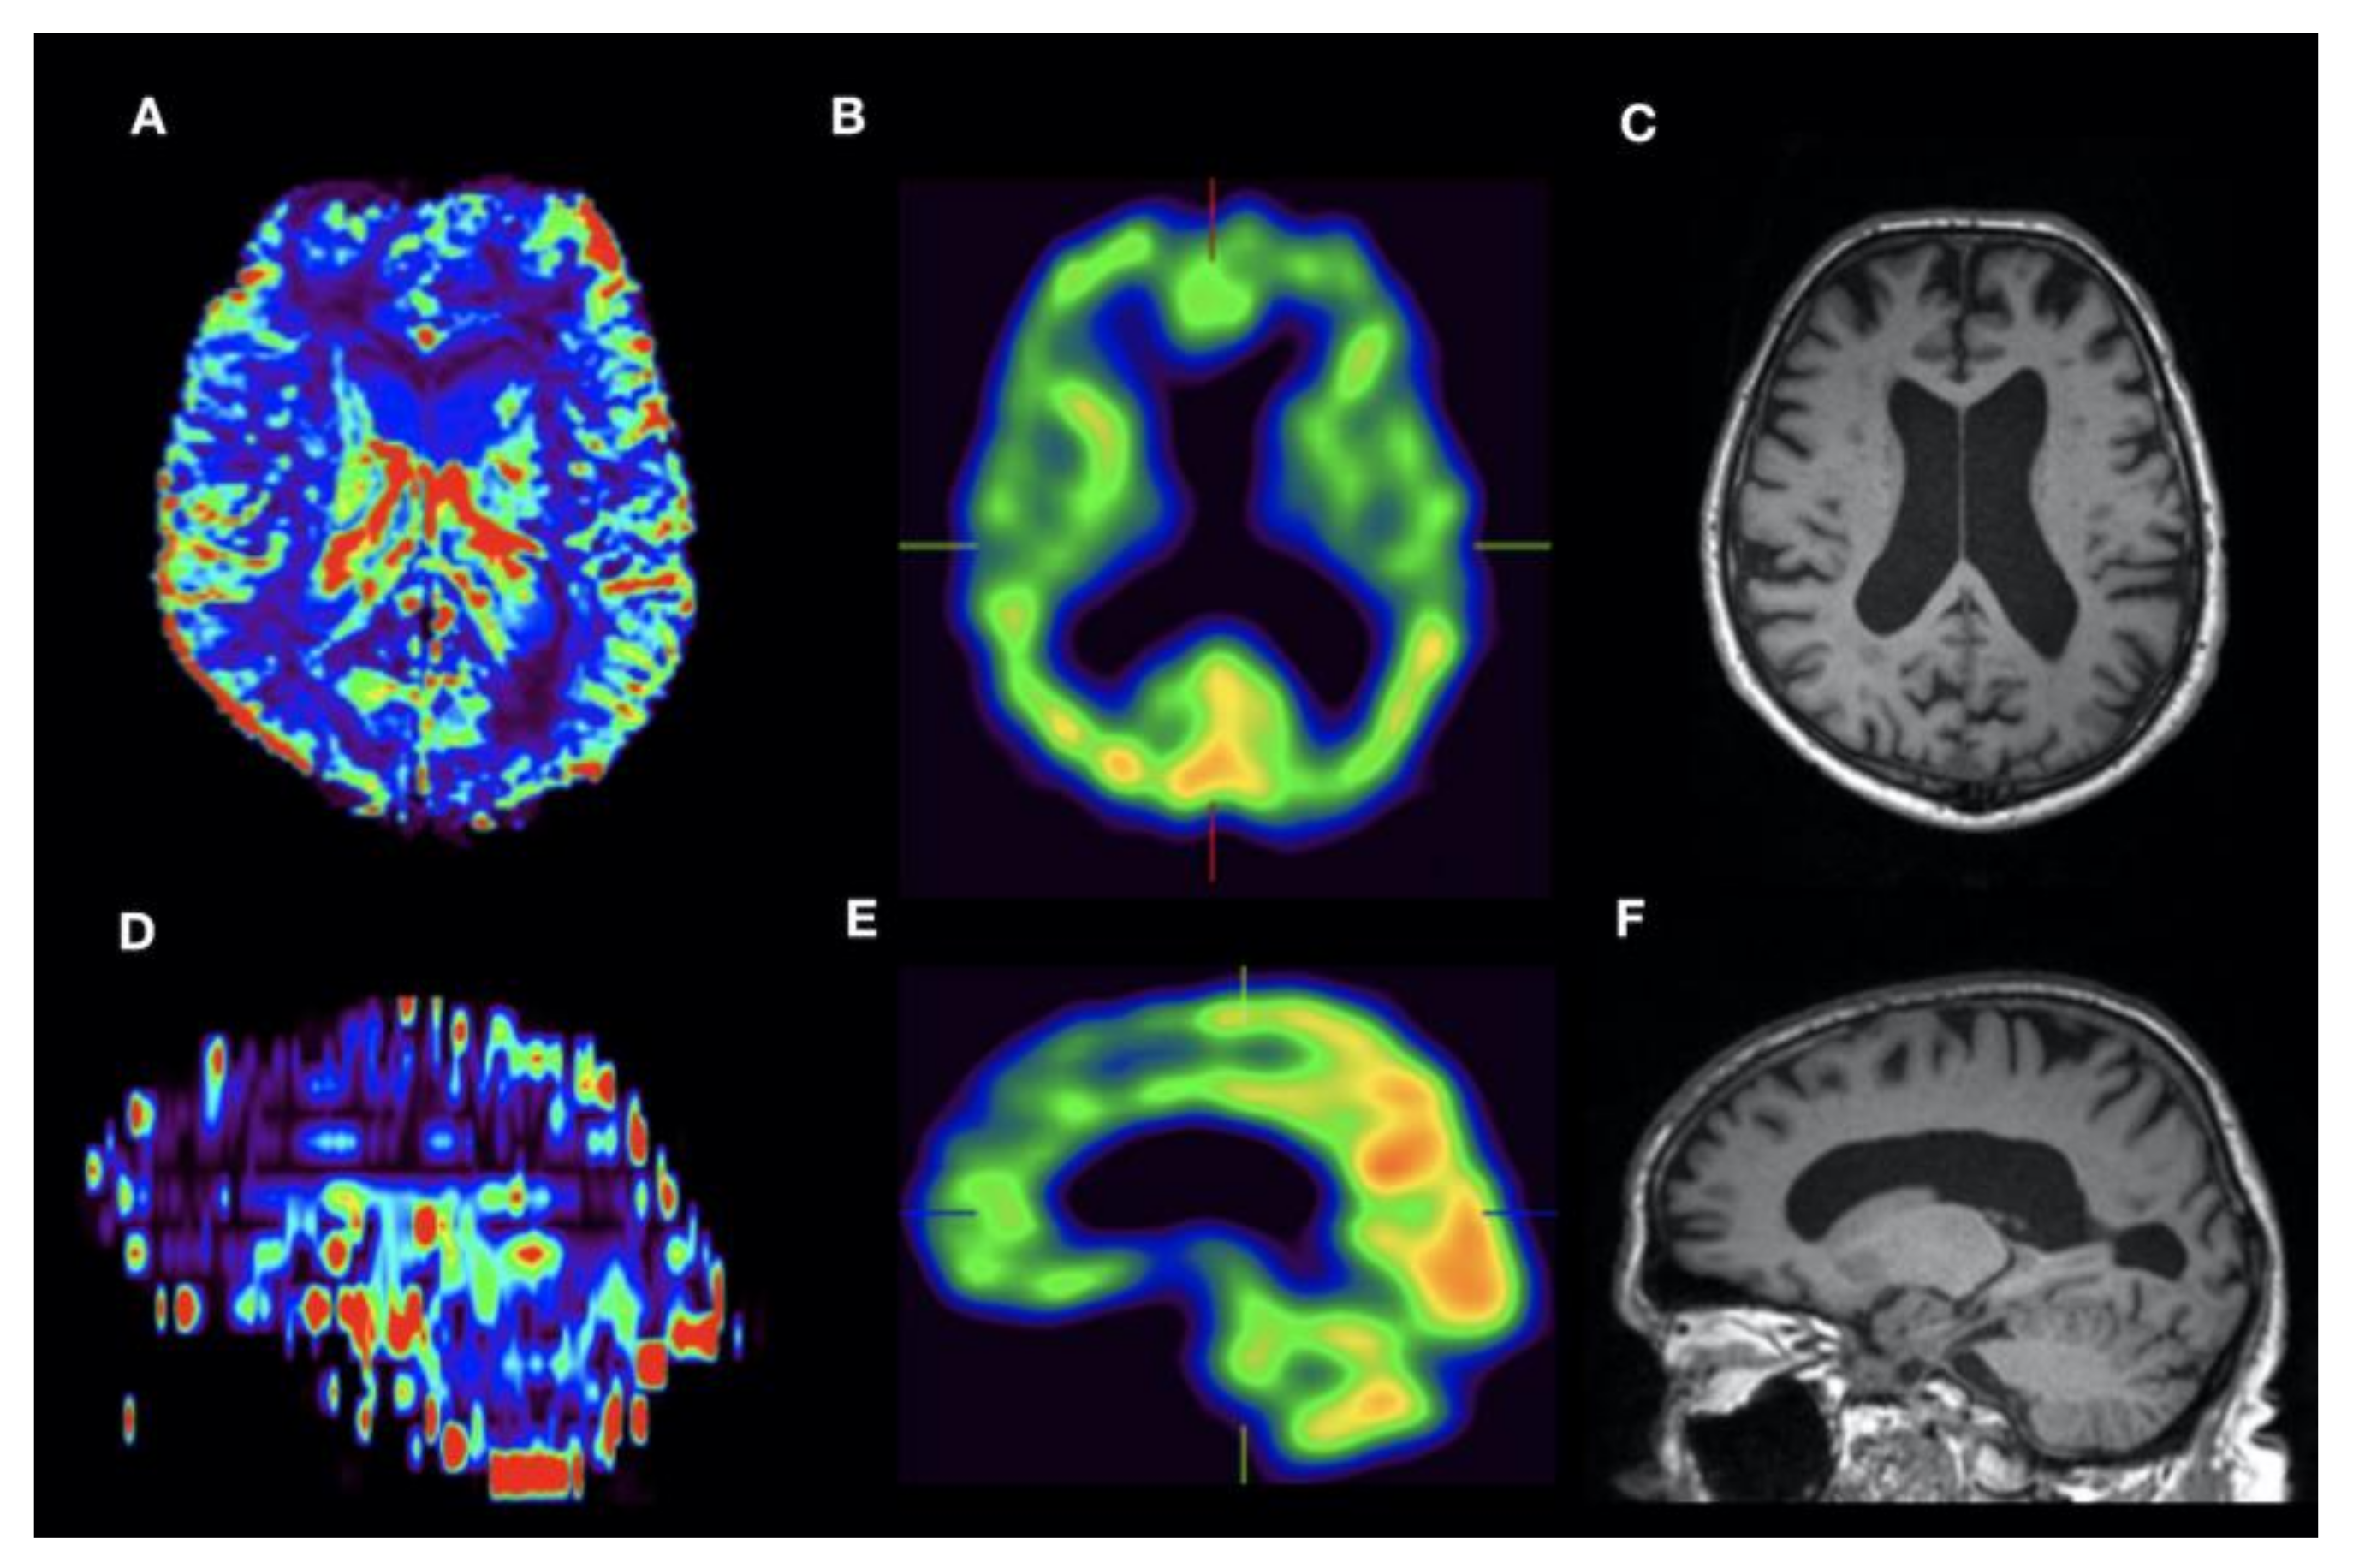

3. Results